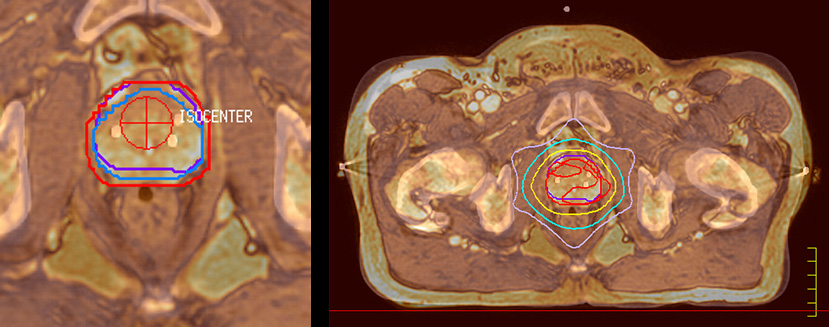

Impressive clinical benefits for prostate

“The biggest problem for CT-based planning, especially in prostate, is you can’t see the cancer very well,” says Dr. Stevens. “On CT it can be quite challenging to see the edge of the prostate especially at the apex. When the edge of the prostate can’t be delineated well on CT, radiation oncologists will increase their margins a little bit so they don’t miss it, but that can also increase toxicity.”

“Using MR, the prostate is well delineated. We quickly see the edges of cancerous tumors like in prostate cancer, and as normal structures can be defined, we can optimize the treatment plan to protect these organs and their normal function. This can potentially improve the outcome. And it improves workflow as well. We can contour more quickly, confident that the tumor is going to be in the field.”